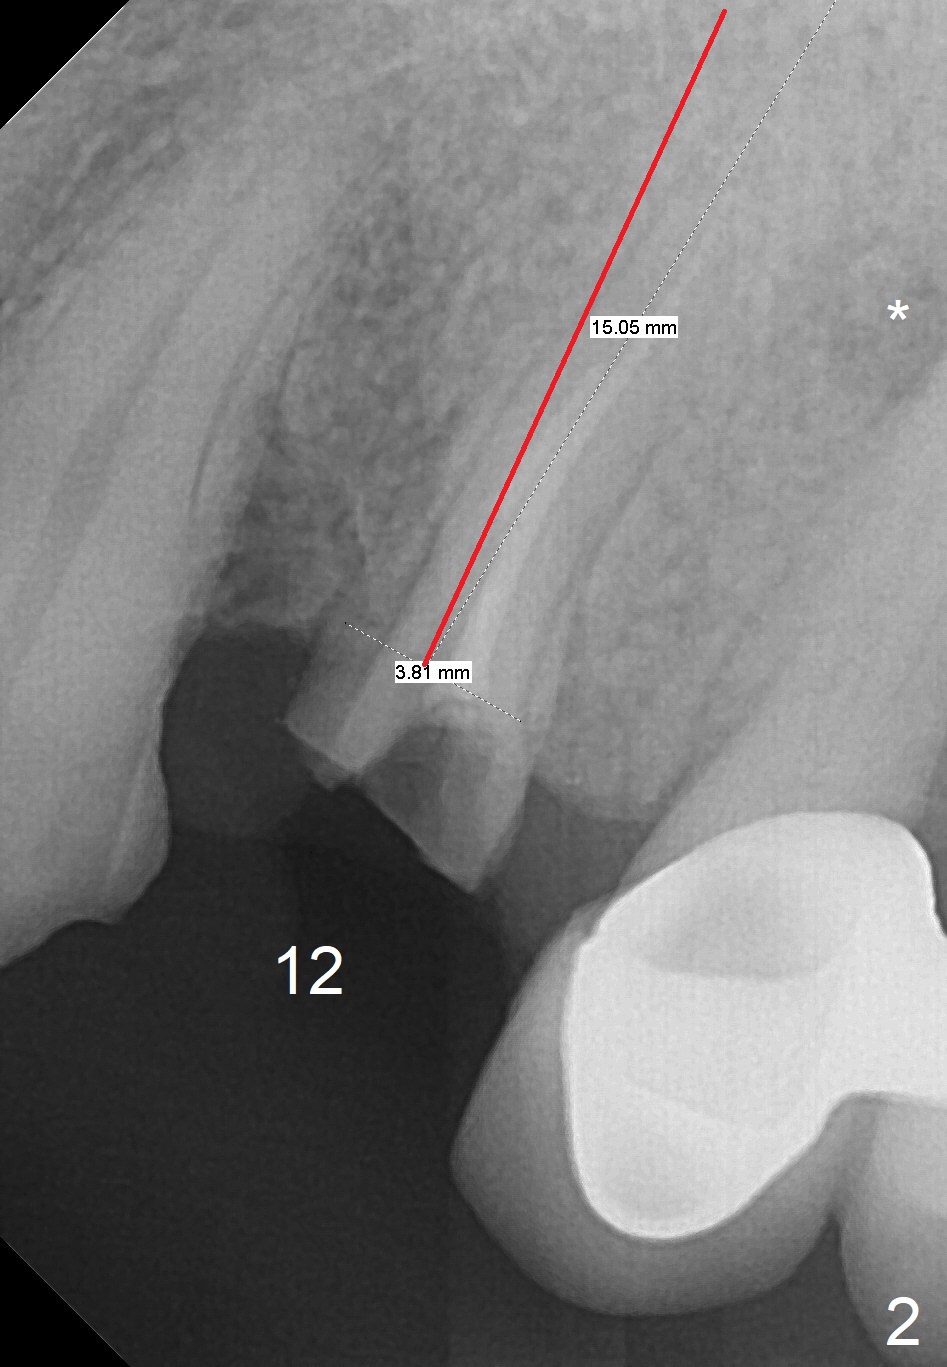

A 75-year-old man came to our office with symptom related to #13-15 FPD 2 months ago (Fig.1). Note periapical radiolucency (PARL, *) associated with the tooth #13. He has a RPD to replace #2 and 3. Last Friday, the crown and post at #12 dislodged (Fig.2). To reduce infection from the neighboring tooth (*), osteotomy will be established in the mesial slope of the socket (red line). The RPD has clasps at #4; the immediate provisional should be wide enough to cover the socket, while it must be skinny enough coronally to avoid contact when the patient puts on and takes off the RPD. The 1st premolar is still in cosmetic zone. If the implant is placed buccal, use a gold-coated abutment. Return to Upper Premolar Immediate Implant, IBS, Clindamycin Xin Wei, DDS, PhD, MS 1st edition 08/25/2017, last revision 11/10/2018